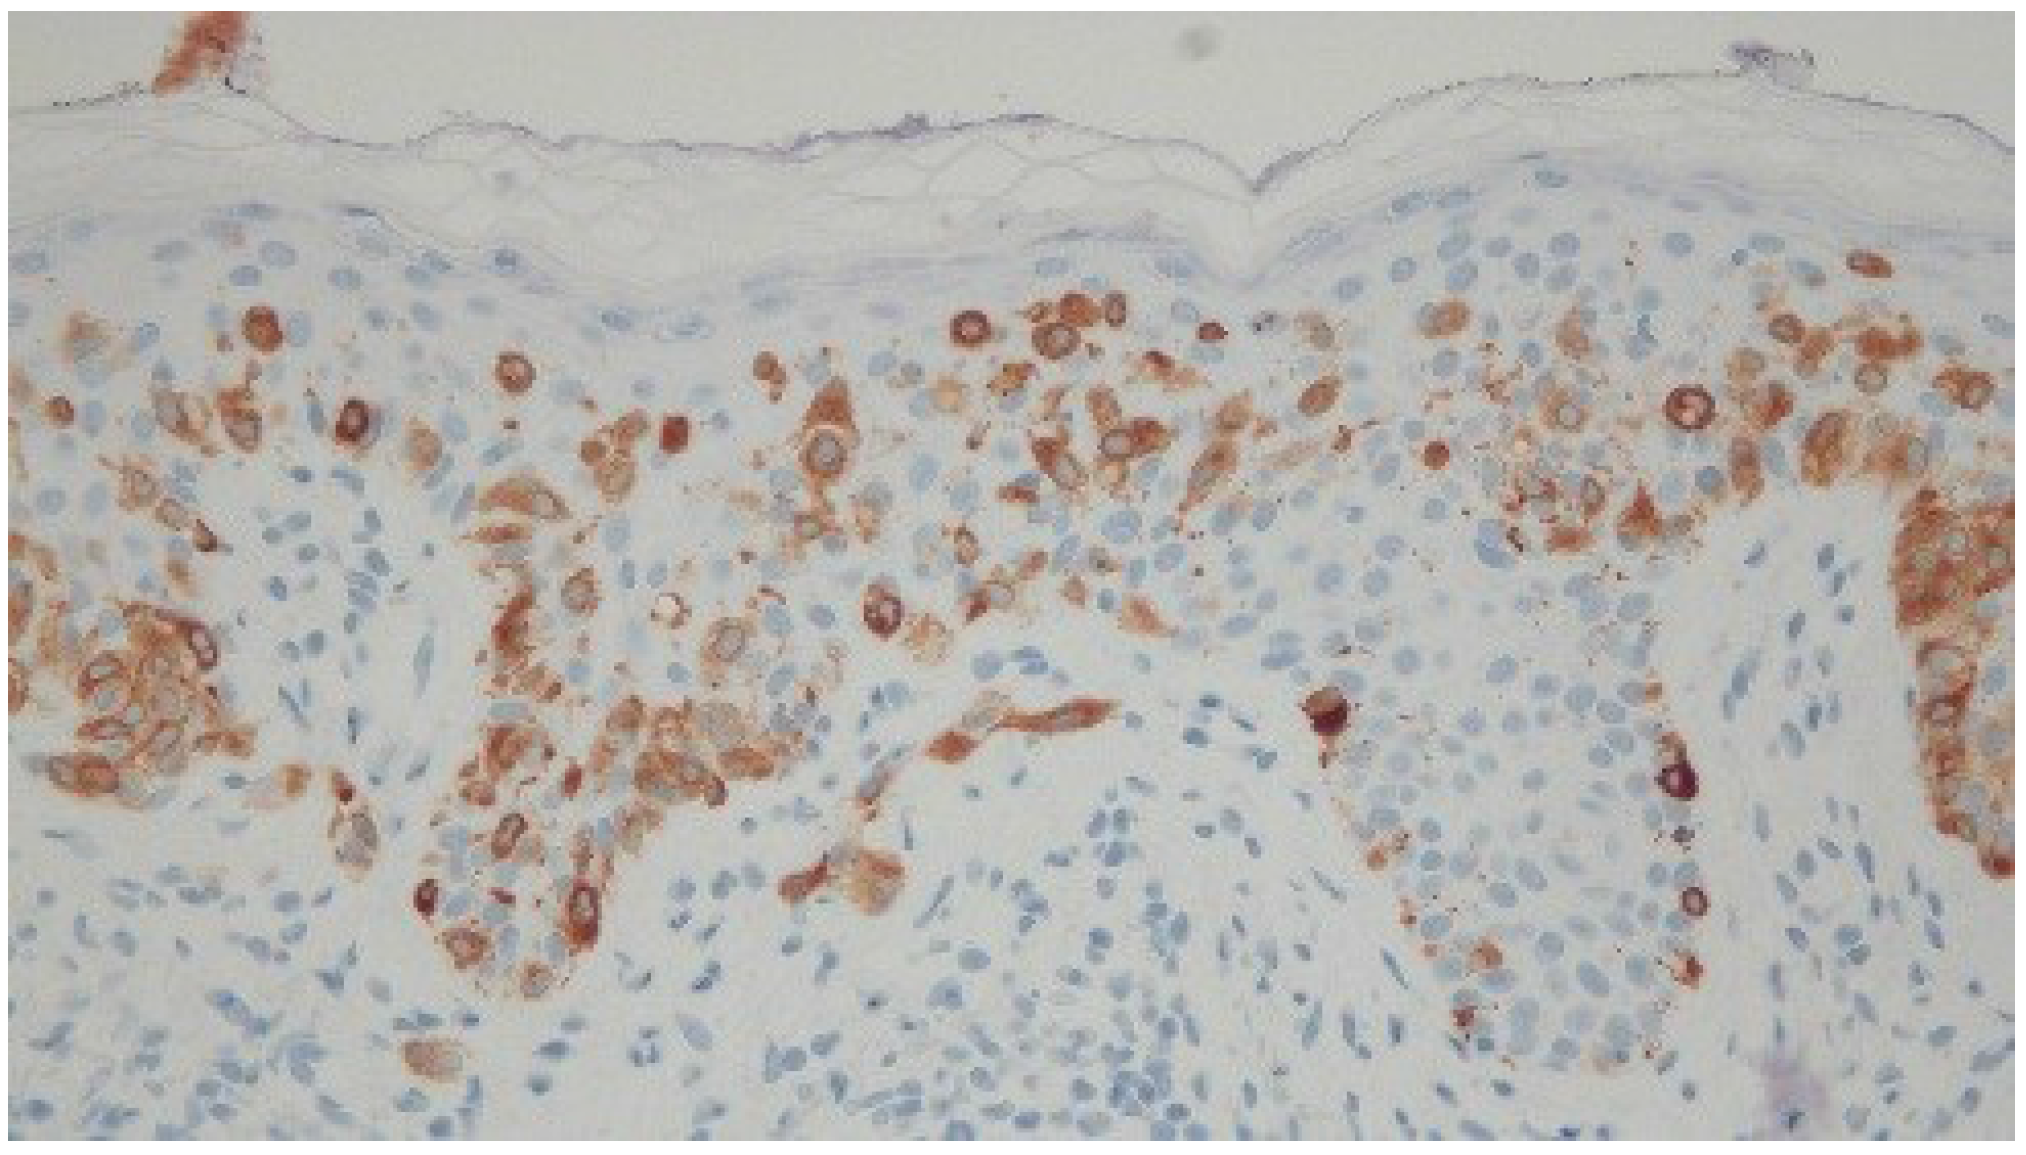

Histologic examination of the tissue from his right antecubital fossa revealed a broad proliferation of moderately atypical melanocytes arranged as both irregular-sized nests and single cells along the dermal-epidermal junction (Figure 3). Areas of contiguous single cell growth as well as a high level pagetoid spread were highlighted by Melanoma Antigen Recognized by T Cell 1 (MART-1) immunohistochemical staining. The pagetoid melanocytes stained negatively for cytokeratin Anion Exchanger Isoforms 1-3 (AE1/3). A small focus of bland-appearing nevoid melanocytes could also be seen in the superficial papillary dermis (Figure 4). The findings were consistent with melanoma in situ arising in the context of a compound nevus. The lesion was excised without complication or recurrence.

Figure 4. High magnification view of a sample of a lesion taken from the right antecubital fossa of a 54-year-old man. Areas of contiguous single cell growth as well as a high level pagetoid spread are highlighted by Melanoma Antigen Recognized by T Cell 1 (MART-1) immunohistochemical staining. The pagetoid melanocytes stained negatively for cytokeratin Anion Exchanger Isoforms 1-3 (AE1/3). A small focus of bland-appearing nevoid melanocytes can also be seen in the superficial papillary dermis. [Melanoma Antigen Recognized by T Cell 1; ×40].